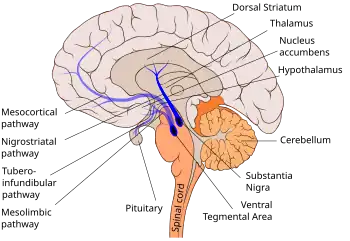

The nigrostriatal pathway is shown here in solid blue, connecting the substantia nigra with the dorsal striatum.

The nigrostriatal pathway is a bilateral dopaminergic pathway in the brain that connects the substantia nigra pars compacta (SNc) in the midbrain with the dorsal striatum (i.e., the caudate nucleus and putamen) in the forebrain. It is one of the four major dopamine pathways in the brain, and is critical in the production of movement as part of a system called the basal ganglia motor loop. Dopaminergic neurons of this pathway release dopamine from axon terminals that synapse onto GABAergic medium spiny neurons (MSNs), also known as spiny projection neurons (SPNs),[1][2] located in the striatum.

Basal ganglia connections showing direct and indirect pathways for movement. The nigrostriatal dopamine pathway is shown in pink.